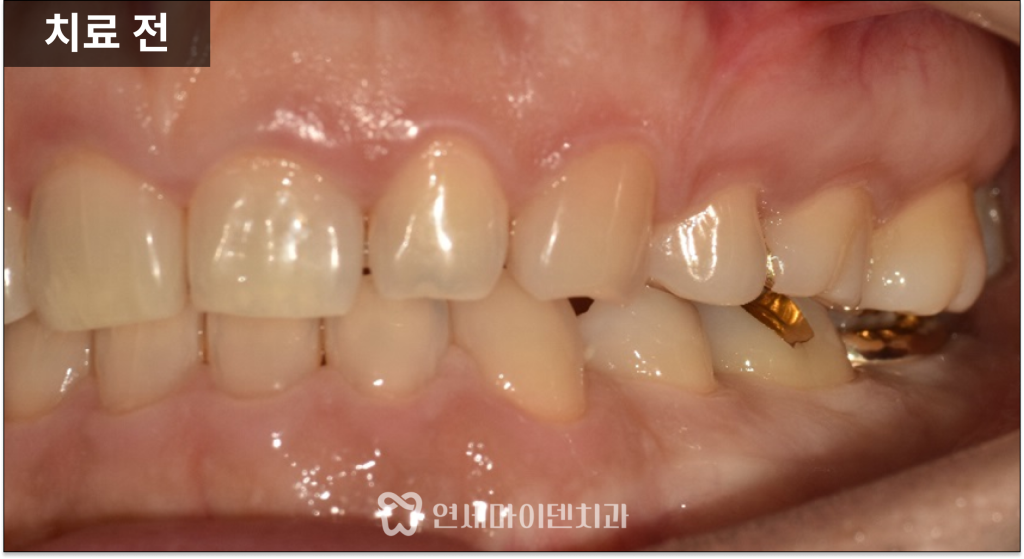

왼쪽 아래 어금니에서

냄새가 나고 흔들리는 증상으로

내원하신 케이스입니다.

잇몸에는 고름이 배출되는

이른바 ‘잇몸 여드름’이 관찰되었습니다.

이러한 증상은 단순한 불편감이 아니라

치아 내부 또는 주변 뼈에서

염증이 지속되고 있다는 신호입니다.